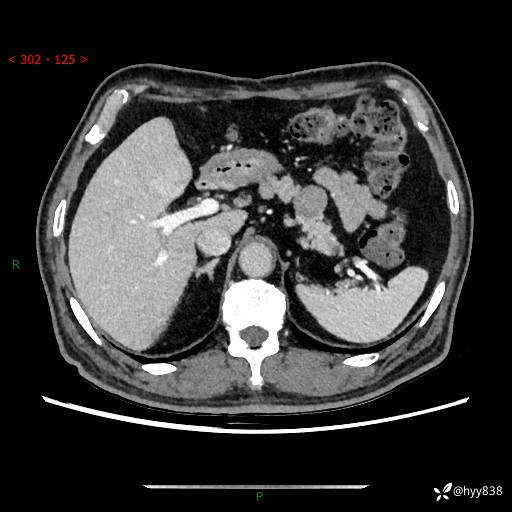

69岁/男,四肢无力3月余。胰腺囊实性占位,渐进性强化---结果公布~

【患者信息】:69岁/男

【主诉】:四肢无力3月余。

【现病史及既往史】:患者3月前无明显诱因出现四肢乏力,伴有口干、多饮、多尿等症状,无畏寒、发热、恶心、腹痛、腹泻等其他症状,于2024-06-13来我院住院治疗,完善相关辅助检查后,考虑“2型糖尿病”,予以降糖(阿卡波糖片 50mg po tid、德谷门冬双胰岛素注射液 8iu 早餐前 皮下注射)等治疗,口干、多饮、多尿较前缓解,血糖控制可;现仍存在四肢乏力,于2024-08-28来我院门诊就诊,查血钾2.88 mmol/L ,现以“低钾血症”收入我科。 本次起病以来,患者精神、饮食、睡眠良好,二便正常,近3月余体重下降约5kg。

【检查】:胰腺CT平扫+增强